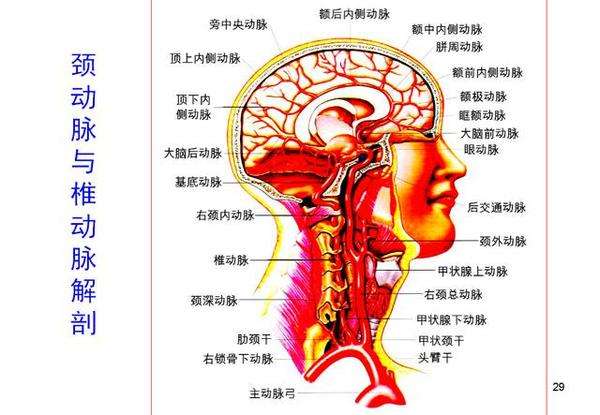

颈动脉与椎动脉解剖图